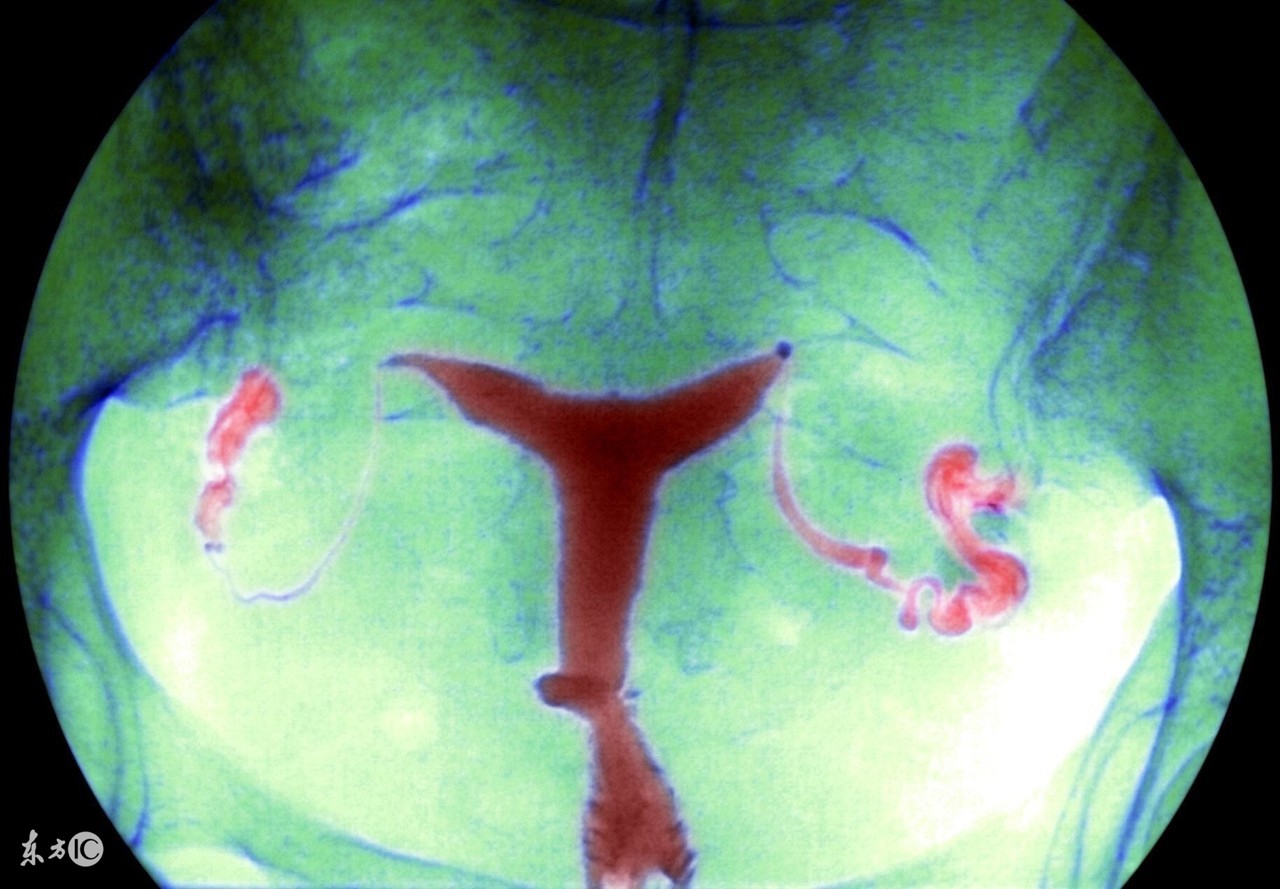

盆腔炎是女性常见的一种疾病,可分为慢性和急性。生活中,慢性盆腔炎比较常见,这种病在病发时可能会伴随着一些低热,病人会觉得自己总是感到疲劳,但是因为全身上下的症状并没有很明显,所以难以引起注意。

慢性盆腔炎可能会引起下腹坠痛,这是盆腔出血或者瘢痕粘连导致,特别是在女性在劳累,月经前后情况会有所加剧。在生活中不乏有女性因为慢性盆腔炎的诊治不及时,最后导致了不孕不育。如果想要预防盆腔炎,就需要做到以下几点: